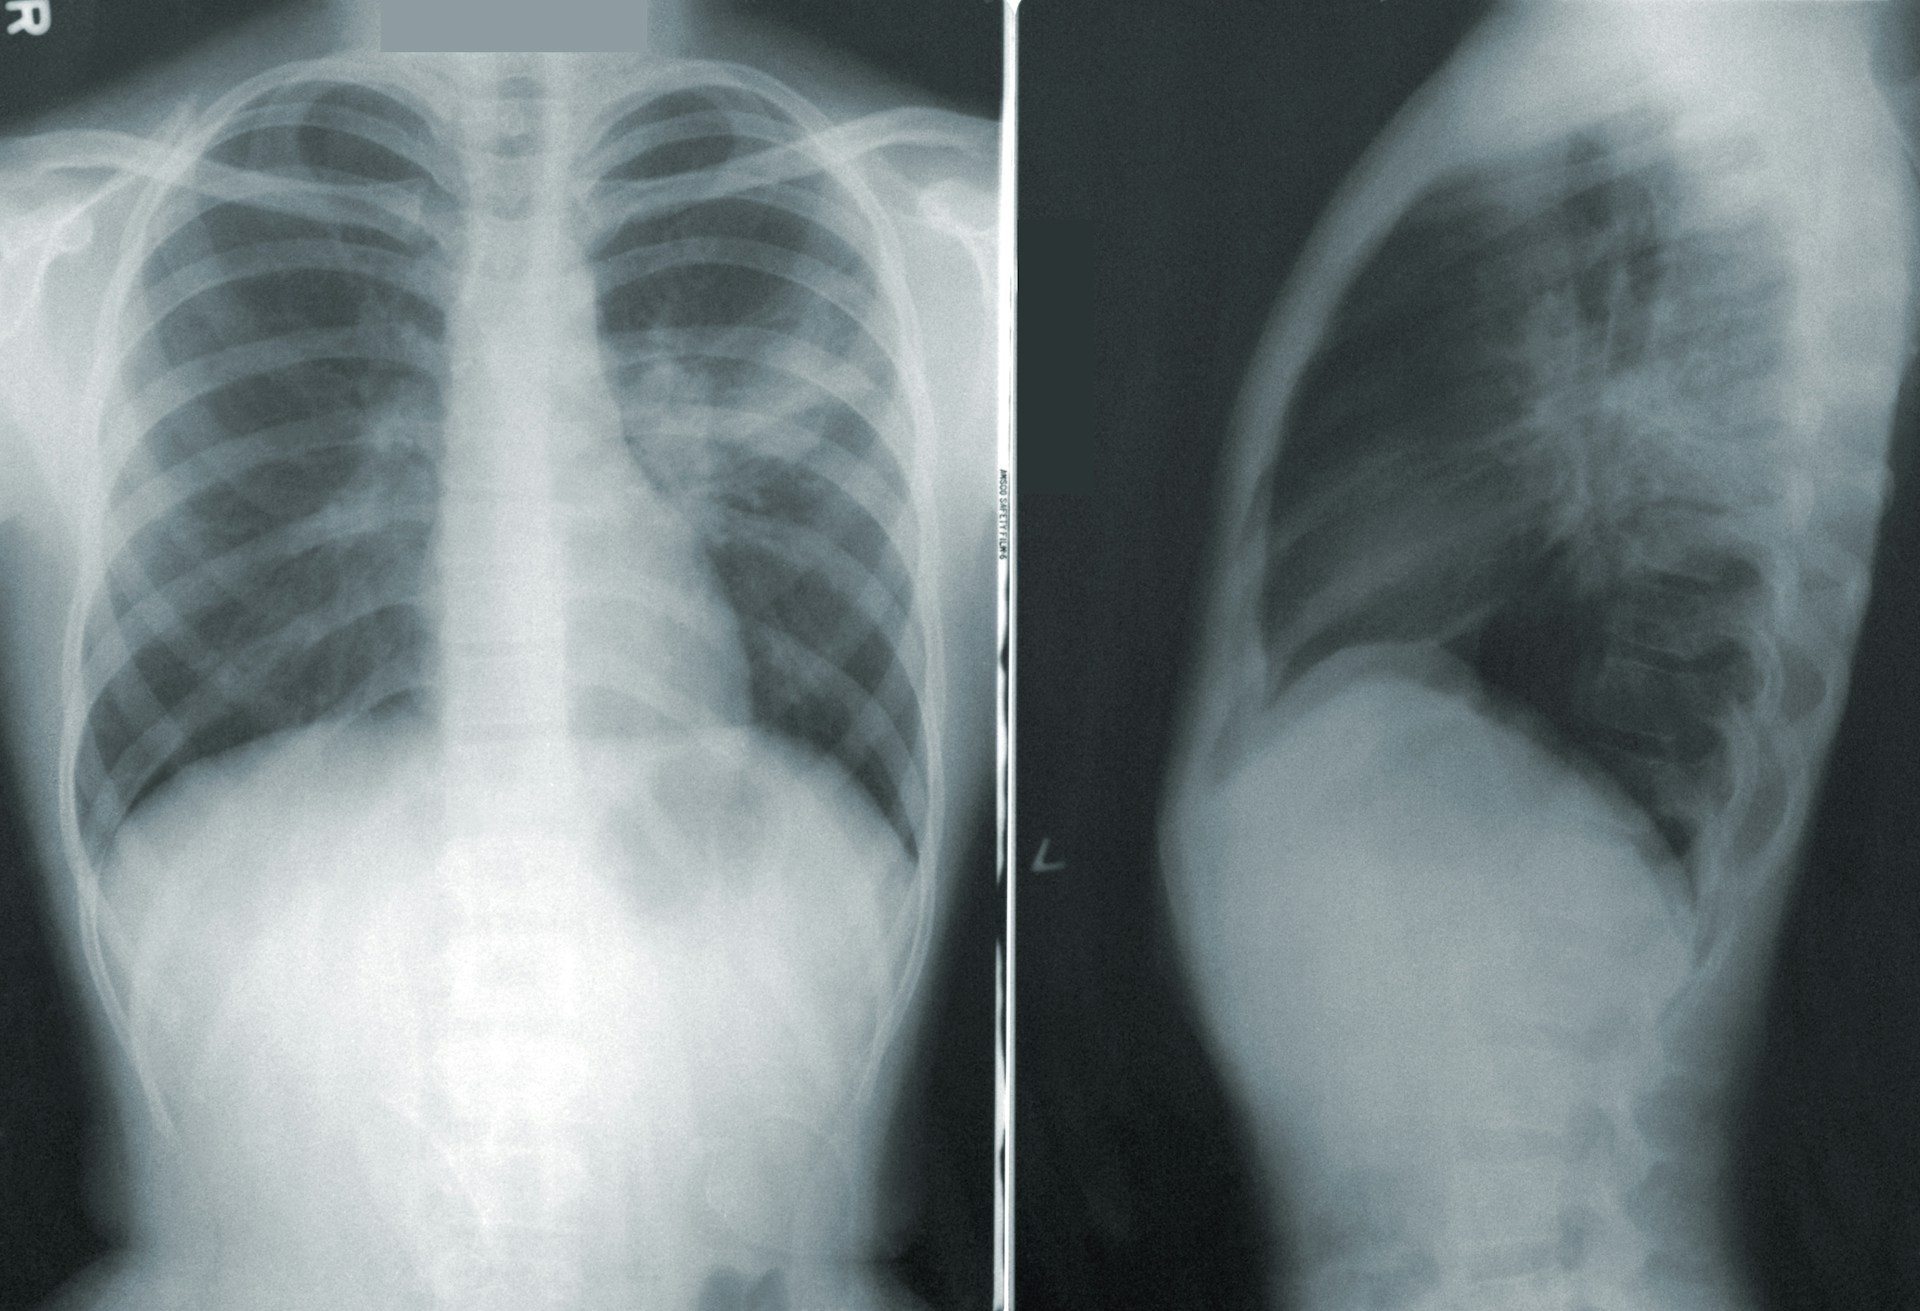

[1단계: 급성폐렴이란?]급성폐렴(acute pneumonia)은 폐의 조직에 급격한 염증이 생기는 호흡기 질환으로, 바이러스, 세균, 진균 등 다양한 병원체에 의해 발생합니다. 감염 원인에 따라 증상이 다르지만, 보통 고열, 기침, 가래, 숨 가쁨 등의 증상이 대표적으로 나타납니다. 면역력이 약해진 시기나 독감이 유행하는 계절에는 발병 위험이 특히 높습니다. 무엇보다 급성폐렴은 진행 속도가 빠를 수 있어, 조기 발견과 적절한 치료가 매우 중요합니다. 특히 노인, 영유아, 그리고 심장질환이나 당뇨와 같은 기저질환이 있는 경우에는 증상이 빠르게 악화되거나 합병증이 생길 수 있으므로 각별한 주의가 필요합니다. 또한 폐렴은 정확한 진단 없이 감기나 독감으로 잘못 생각하기 쉬워, 치료가 지연될 수도 있습니다. ..